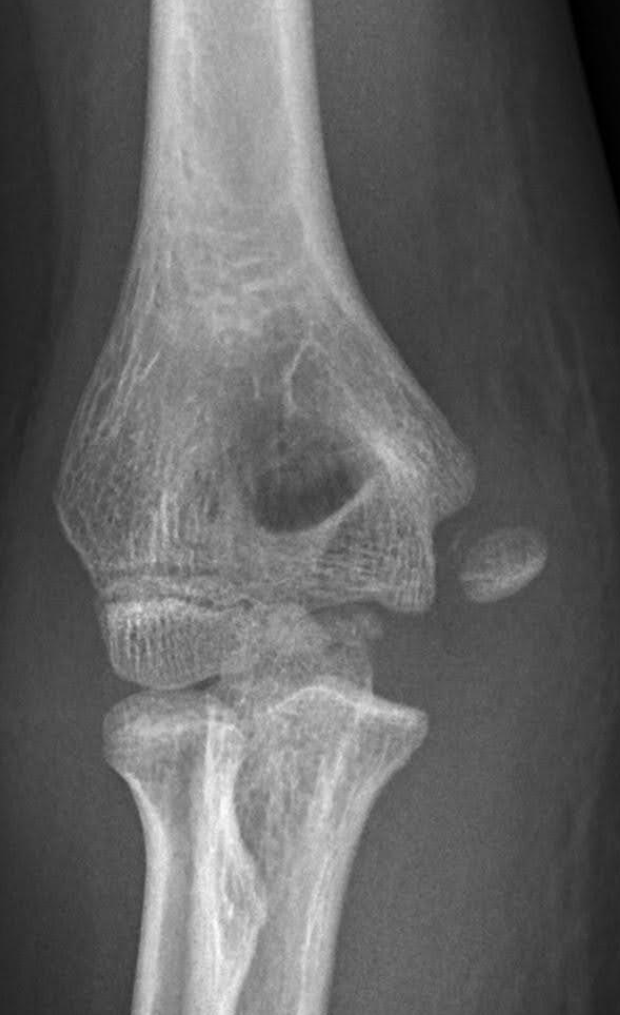

I Felt a Pop and My Elbow Hurts...

A 13-year-old male presents with acute onset of medial elbow pain after throwing a football, at which time he felt a ‘pop’ and is now unable to fully extend at the elbow. He is tender to palpation at the medial epicondyle. He has a history of Little Leaguer’s Elbow.

A 14-year-old male presents for left medial elbow pain after pitching during a baseball game the night before when he felt a snap in his left elbow during a pitch. He continued to feel a sharp pain with every subsequent pitch in the medial elbow. He has point tenderness on the medial aspect of his left elbow and pain with elbow extension but full ROM. He has tried OTC anti-inflammatory medications and icing at home with mild relief.

Read More...